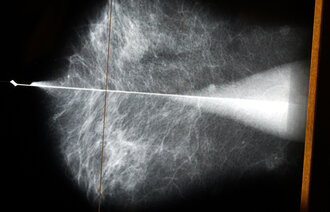

Flere brystkreftpasienter får tilgang til legemiddelet EnhertuI

Fra 1. november vil rundt 250 flere pasienter med brystkreft kunne behandles med legemiddelet Trastuzumabderukstekan (Enhertu).

Enhertu som behandling mot brystkreft har i studier vist doblet progresjonsfri overlevelse sammenlignet med standardbehandling, og forbedret totaloverlevelse på over et halvt år, og legemiddelet ble i fjor innført til pasienter med aggressiv brystkreft.

Nå har Beslutningsforum åpnet for at det også kan brukes som behandling til pasienter med inoperabel eller metastaserende HER2-lav brystkreft fra 1. november, anslagsvis 250 hvert år.

Inoperabel eller metastatisk brystkreft vil si når kreftsvulsten ikke kan fjernes kirurgisk eller har spredd seg til andre steder i kroppen. Norge blir først ute med dette bruksområdet av land vi vanligvis sammenligner oss med – som Danmark, Sverige og England.